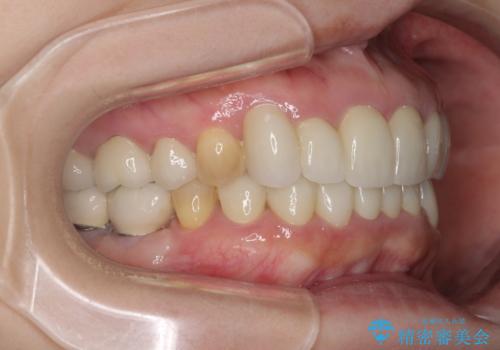

- 下顎の前歯に激痛を覚えて来院された患者様です。

取り急ぎ下顎前歯数歯の根管治療を、銀座しらゆり歯科医院長の林先生にお願いし、それ以外に気になっている、不自然な色調のクラウン、金属部分が見えてブラッシングがしにくいインプラント補綴、口元の突出感、出血のしやすい歯周ポケットなど、全てを解決するための治療を行うこととしました。

期間と費用はかかりましたが、気になっていた部分全てを改善でき、患者様には大変満足していただきました。